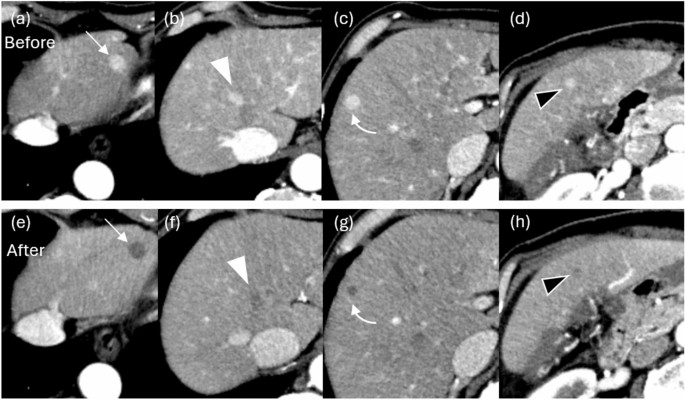

Arterial phase of contrast-enhanced CT before (a, b, c, d) and after (e, f, g, h) BOAI-TACE in a 78-year-old man. Seven HCCs were found in the liver, including a 14 mm hepatocellular carcinoma (HCC) in S3 (arrow), a 13 mm HCC in S4/8 (white arrowhead), a 11 mm HCC in S8/5 (curved arrow), and a 6 mm HCC in S5 (black arrowhead). After treatment, the contrast effect of all lesions disappeared and complete response was obtained.